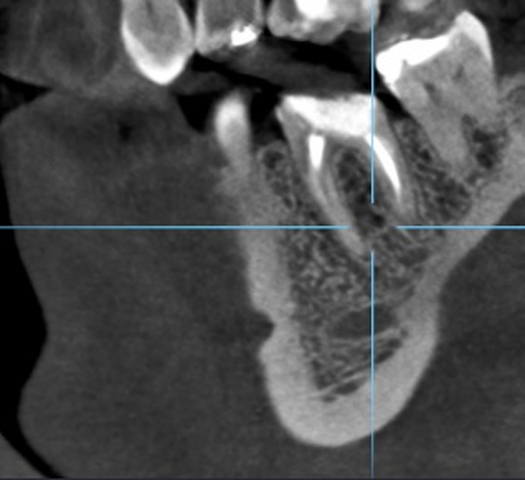

Ryc. 4. Przekrój zęba 36 w płaszczyźnie czołowej. Ryc. 5. Przekrój zęba 36 w płaszczyźnie strzałkowej.

Diagnostykę poszerzono o badanie tomografii wiązki stożkowej (ryc. 4-6). Region implantacji zwymiarowano w trzech płaszczyznach w specjalnym programie komputerowym 3Shape Implant Studio® (3Shape, Kopenhaga, Dania), wykonano szablon implantologiczny i przystąpiono do procedury chirurgicznej. Zaprojektowano użycie wszczepu o wymiarach 4,2 x 10 mm.